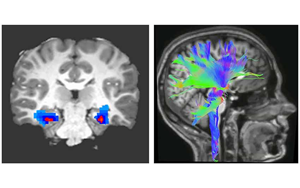

貝勒醫(yī)學(xué)院和德克薩斯兒童醫(yī)院最近的一項(xiàng)研究確定了一種特定的神經(jīng)活動(dòng)模式,作為一種新的生物標(biāo)志物,可以準(zhǔn)確預(yù)測和監(jiān)測接受深部腦刺激(DBS)治療的強(qiáng)迫癥(OCD)患者的臨床狀態(tài),深部腦刺激是一種迅速出現(xiàn)的治療嚴(yán)重精神疾病的方法。